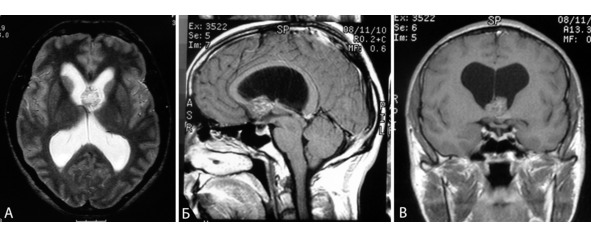

Рисунок 16. МРТ больного с объемным образованием межжелудочковой перегородки, колонок свода и гипоталамической области, больше слева. Дооперационный диагноз – опухоль. Диагноз «кавернома» поставлен по данным морфологического исследования. А – режим Т2 в аксиальной плоскости, Б – режим Т1 в сагиттальной плоскости, В – режим Т1 во фронтальной плоскости.

Рисунок 17. МРТ больной с каверномой латеральных отделов центральной борозды слева. Дифференциальный диагноз – кавернома или тромбированная аневризма. Патоморфологическое заключение – кавернома. А – режим Т1 в аксиальной проекции, Б – режим Т2 в аксиальной проекции, В – режим FLAIR в аксиальной проекции.